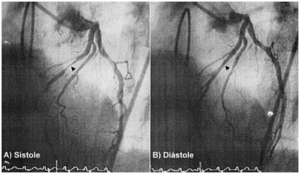

Varón de 61 años que ingresa por dolor precordial en reposo junto con elevación del segmento ST en la pared inferior. Tras el alivio del dolor torácico con nitroglicerina, el electrocardiograma y la seriación de las enzimas cardíacas fueron normales y, por tanto, el paciente fue diagnosticado de angina variante de Prinzmetal. La arteriografía coronaria, en proyección oblicua anterior izquierda con angulación craneal, mostró un árbol coronario sin lesiones aterosclerosas obstructivas, pero en el tercio medio de la arteria descendente anterior izquierda (flechas) existía un puente miocárdico responsable de una compresión sistólica (A), que desaparecía durante la diástole (B). El puente miocárdico se consideró que era un hallazgo angiográfico casual, sin ninguna influencia en la sintomatología del paciente, pues el dolor precordial no era de esfuerzo (como sucede en los pacientes con puentes miocárdicos sintomáticos) y las alteraciones electrocardiográficas no afectaban a la cara anterior (como correspondería a una lesión en la arteria descendente anterior). El paciente fue tratado con diltiazem y quedó asintomático.